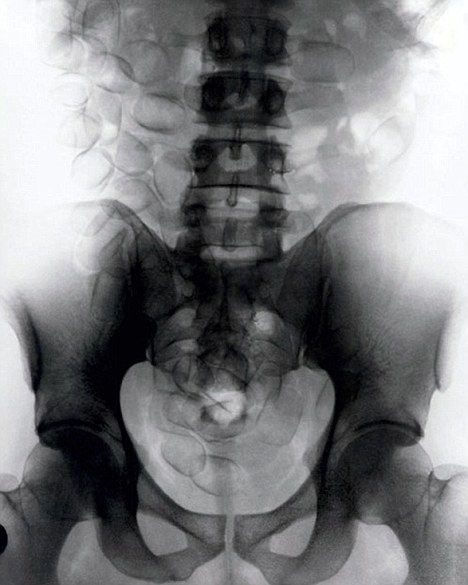

现年30岁的菲达利斯(Fidelis Ozouli)冒着生命危险将重达1公斤的毒品吞下,被抓后却辩称不知道吞下的是毒品。当时,曼彻斯特机场的海关人员看到毒贩菲达利斯臃肿的肚腩,显得很不自然,于是开始怀疑。检查人员用X射线机照他的胃部时,发现了大量可卡因。目前他已被送往附近医院,以确保排出所有的毒品。